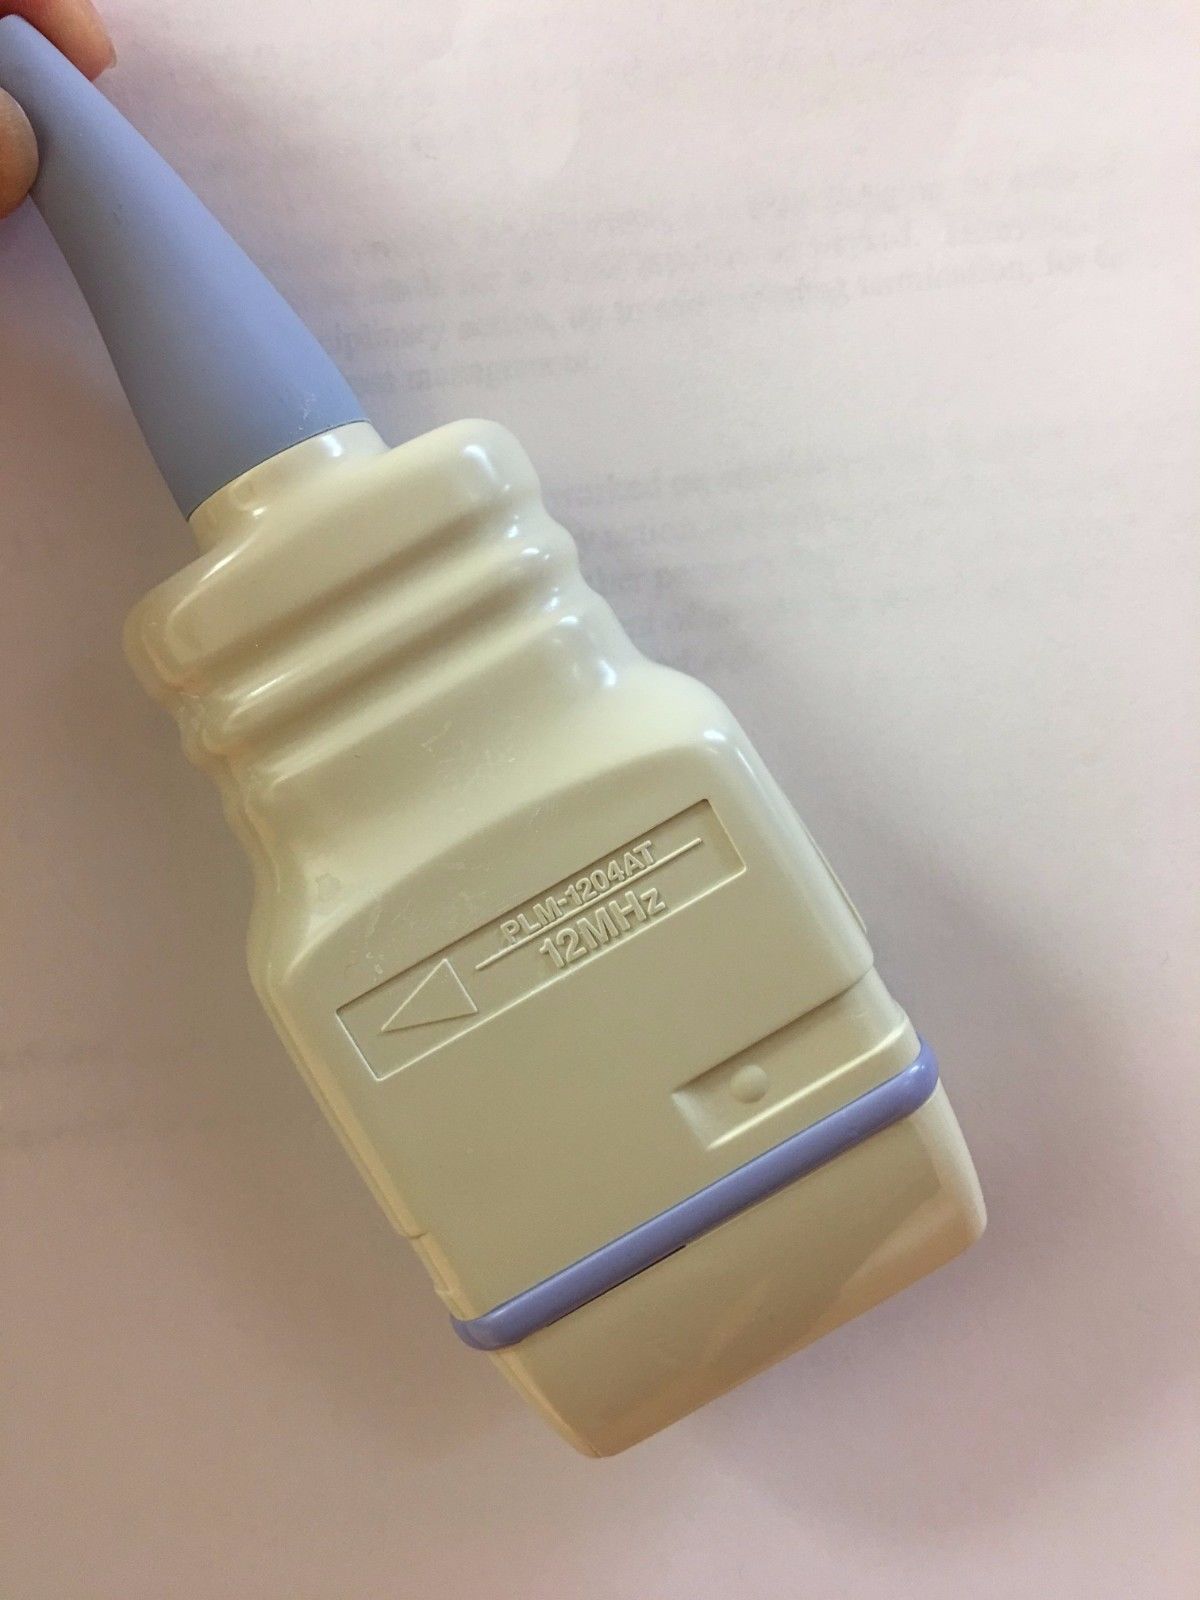

DIAGNOSTIC ULTRASOUND MACHINES FOR SALE

Linear Array L38/10-5Mhz For Sonosite Titan Portable Ultrasound 2013

Sale price$ 1,199.20

Regular price$ 1,499.00